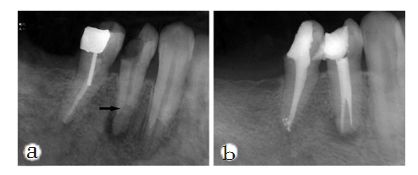

牙齒根管治療中如忽略根管治療,則會導致這個區域根管系統不可以完全清理工作嚴實添充,無法爲齲病和慢性牙髓炎痊愈給予最理想的標准,造成牙齒根管治療不成功。因而,根管治療忽略即是牙齒根管治療裏的錯誤操作之一,也是危害牙齒根管治療愈後的重要因素之一。

主莖管忽略的處理方法